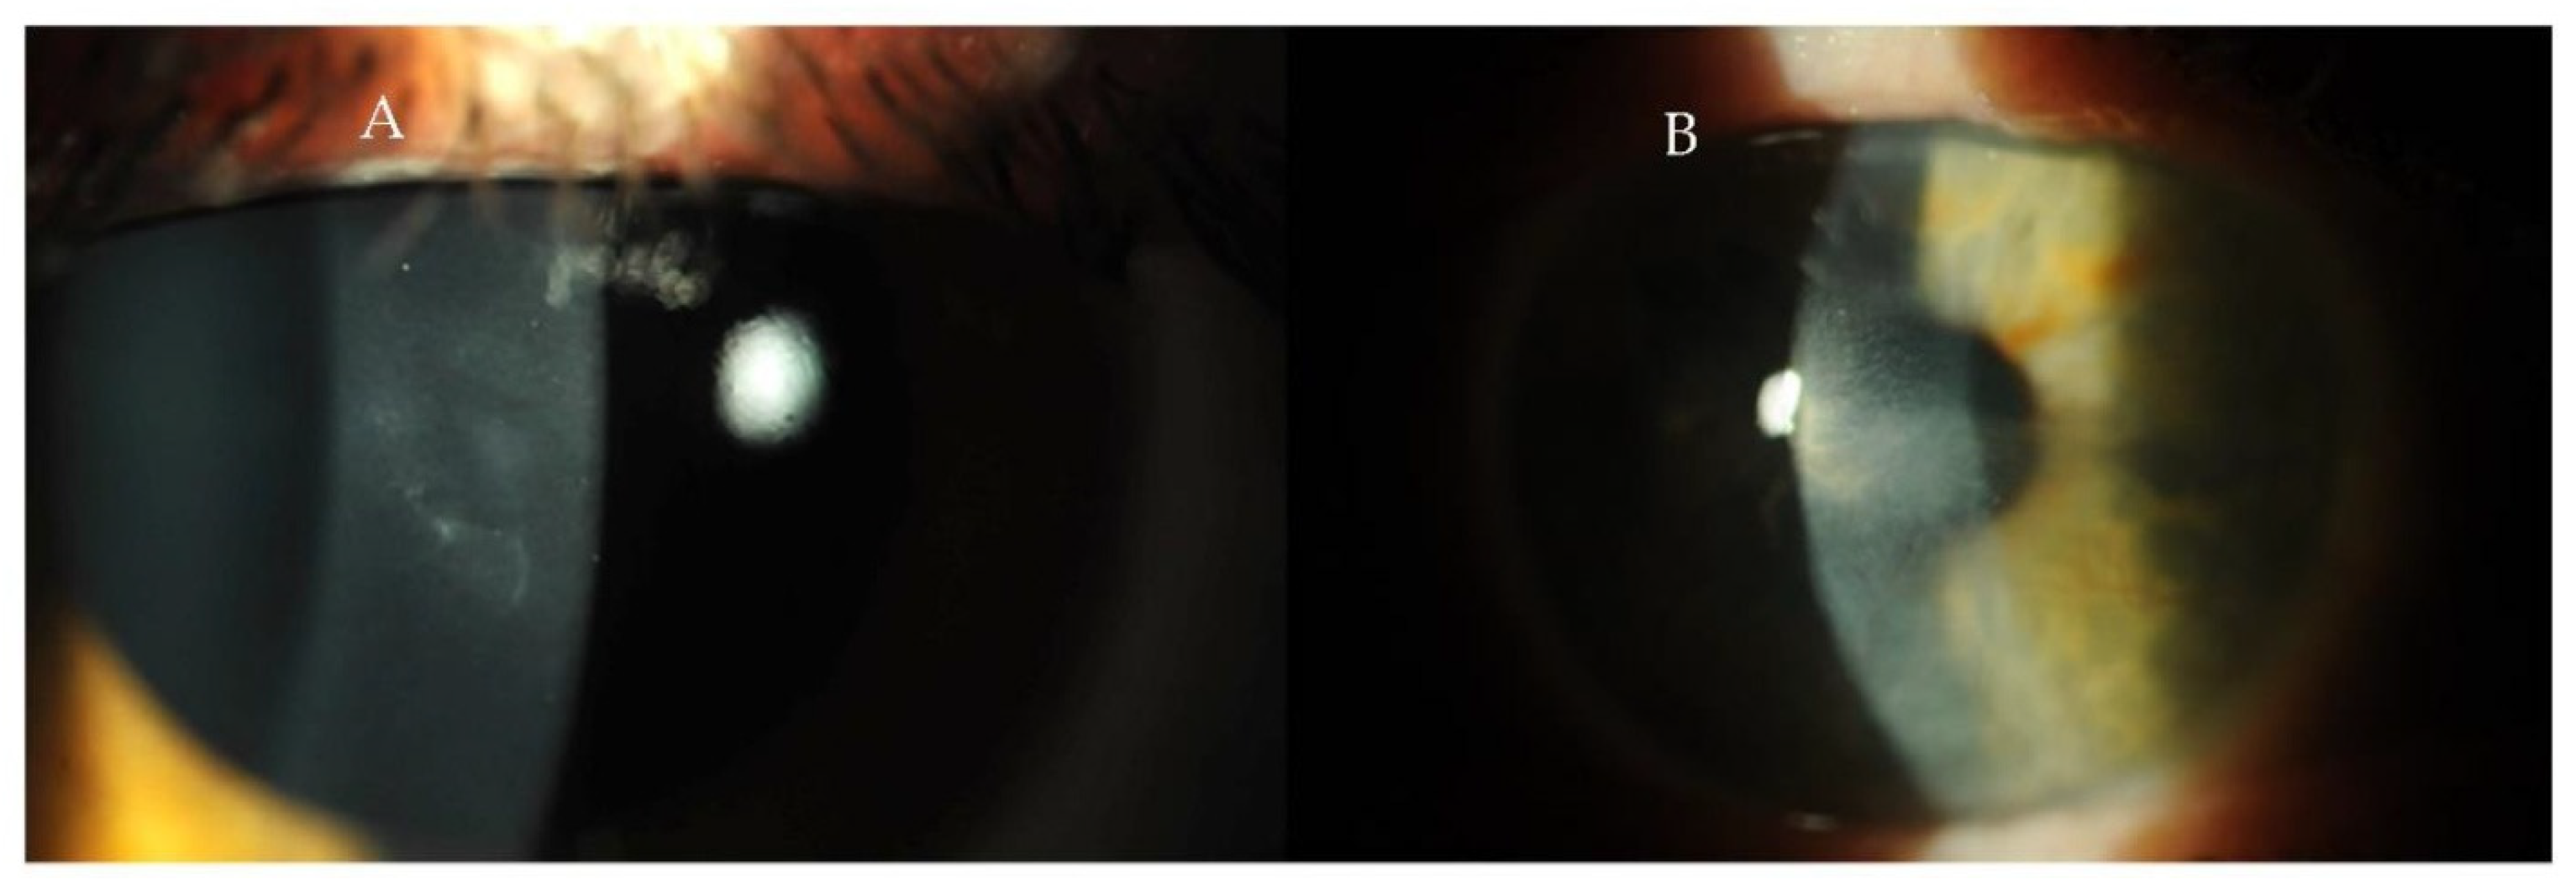

| Hyperparathyroidism | Band keratopathy | Slit-lamp examination | Golan et al. [11] Abeysiri and Sinha [12] | |